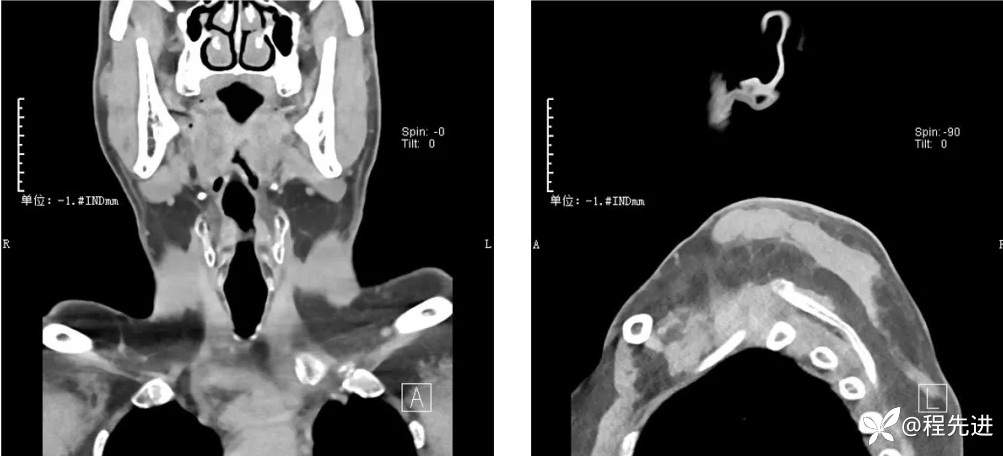

CT检查: